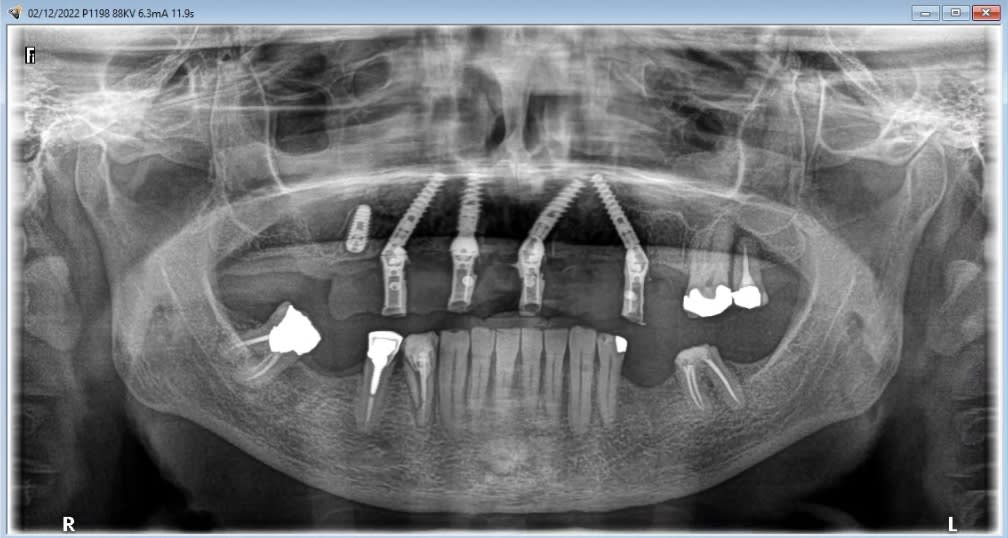

Voilà les photos du cas , avec un peu de retard.

06C757A0-0679-4A5E-A2AD-9E867A3CB080.jpeg

65672A94-F454-46C1-A2A7-47927485B543.jpeg

143DCC8C-EA6F-4EE5-9915-F12A33C377B9.jpeg

F8362BF2-81BC-455C-BFD0-A9FE9451F3F4.jpeg

91CE34AF-EDB6-436D-8B12-726F81FC0CB1.jpeg

4060EC60-1F78-4778-B0E3-5FE470671FDF.jpeg

F4ECCBAA-30DE-407C-AAD1-02D226210CC9.jpeg

C4C89A41-3628-4190-A864-AFFC591089BF.jpeg

Enfin, le cas de la semaine précedente. Guide osseux maison, bridge imprimé. On conserve 26 27. Mais les sinus sont assez antérieurs : on sort au niveau des 4 avec les implants angulés. Malgré le fait de faire un mini comblement sinus droit : l'implant passe la crete, rentre dans le sinus, et retrouve l'os en direction nasal, mais on sort quand meme en 14.

Alors pose d'un implant dans l'alvéole de la 15, aucune stabilité, comblement. A utiliser pour le bridge définitf.